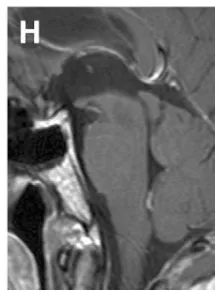

(H)术后2年经幕下小脑上入路全切肿瘤后矢状位T1增强MRI,显示肿瘤全切除,患者无神经功能缺损,恢复良好